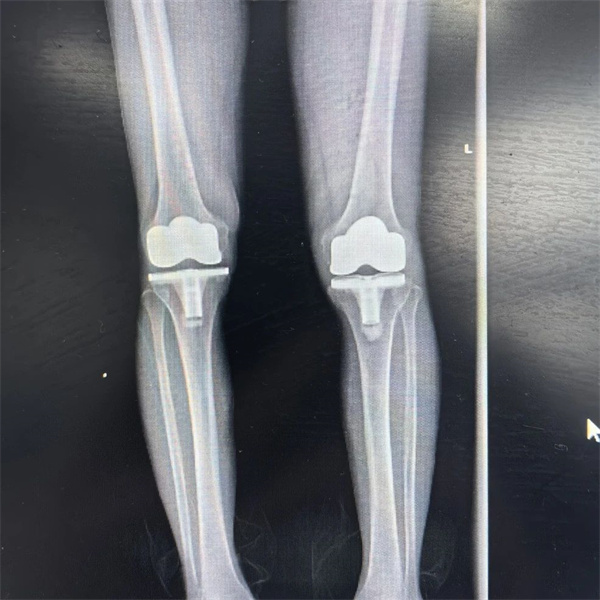

经过多方打听,两夫妻在两年前来到了萍乡市人民医院关节外科做了详细的体格检查,发现夫妻俩双侧膝关节间隙狭窄、骨赘增生,汤伯母的左膝关节还有着较重的内翻畸形,都属于膝骨关节炎,经过保守治疗效果不佳,反复疼痛多年,存在膝关节置换的指征。

汤伯母需要左膝关节置换,而苏伯父双膝都需进行置换。两年前的那次手术,为了更好的互相照顾,不麻烦子女,两夫妻选择一起进行手术。